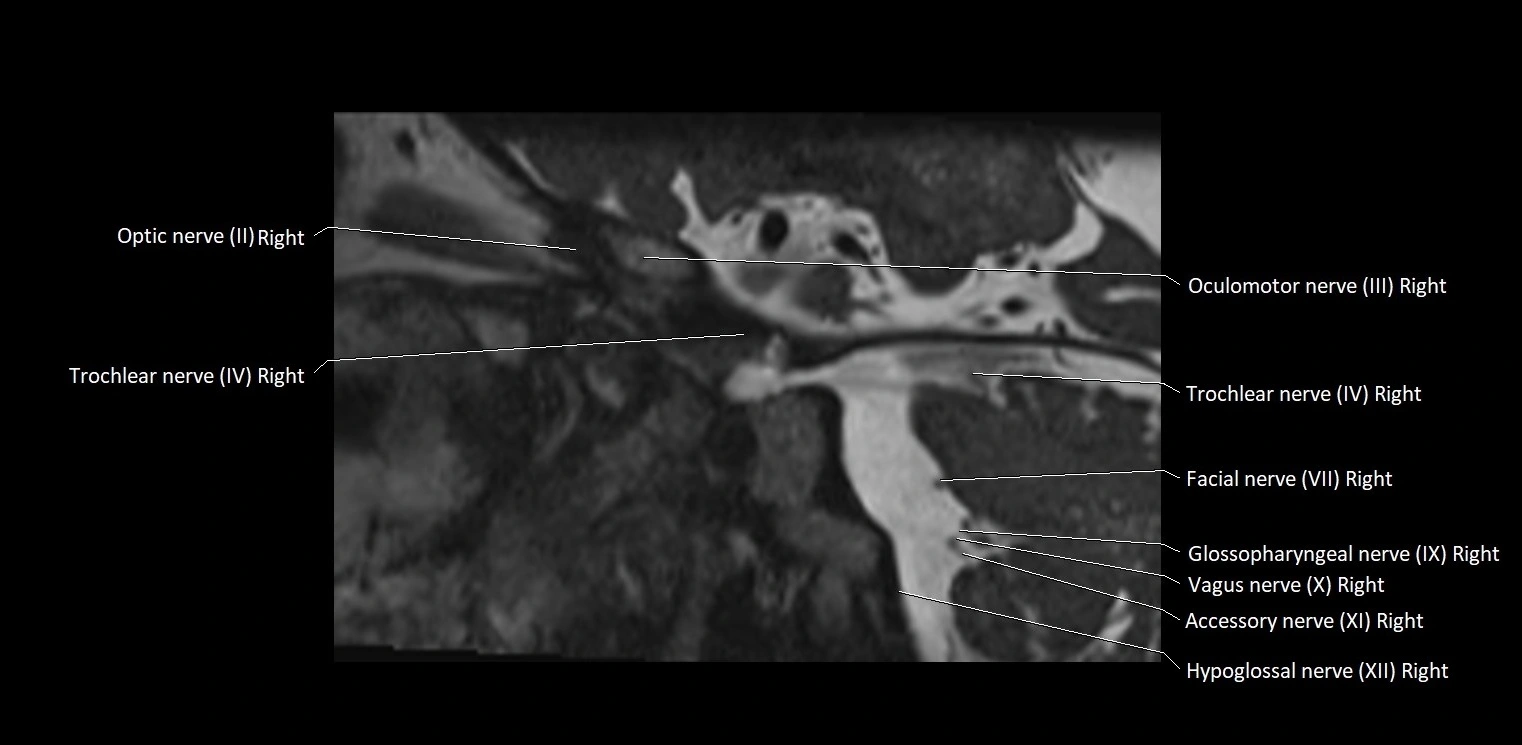

MRI Appearance

• The abducens nerve is a small, thin, linear structure

• Best visualized on high-resolution T2-weighted 3D MRI sequences (e.g., FIESTA or CISS)

• Seen as a hypointense (dark) line running from the brainstem at the pontomedullary junction, traversing the prepontine cistern, and entering Dorello’s canal under the petrosphenoidal ligament, then into the cavernous sinus, and finally the orbit

• May be challenging to visualize in standard MRI due to its small size

• Pathology may be inferred by absence, displacement, or enhancement of the nerve